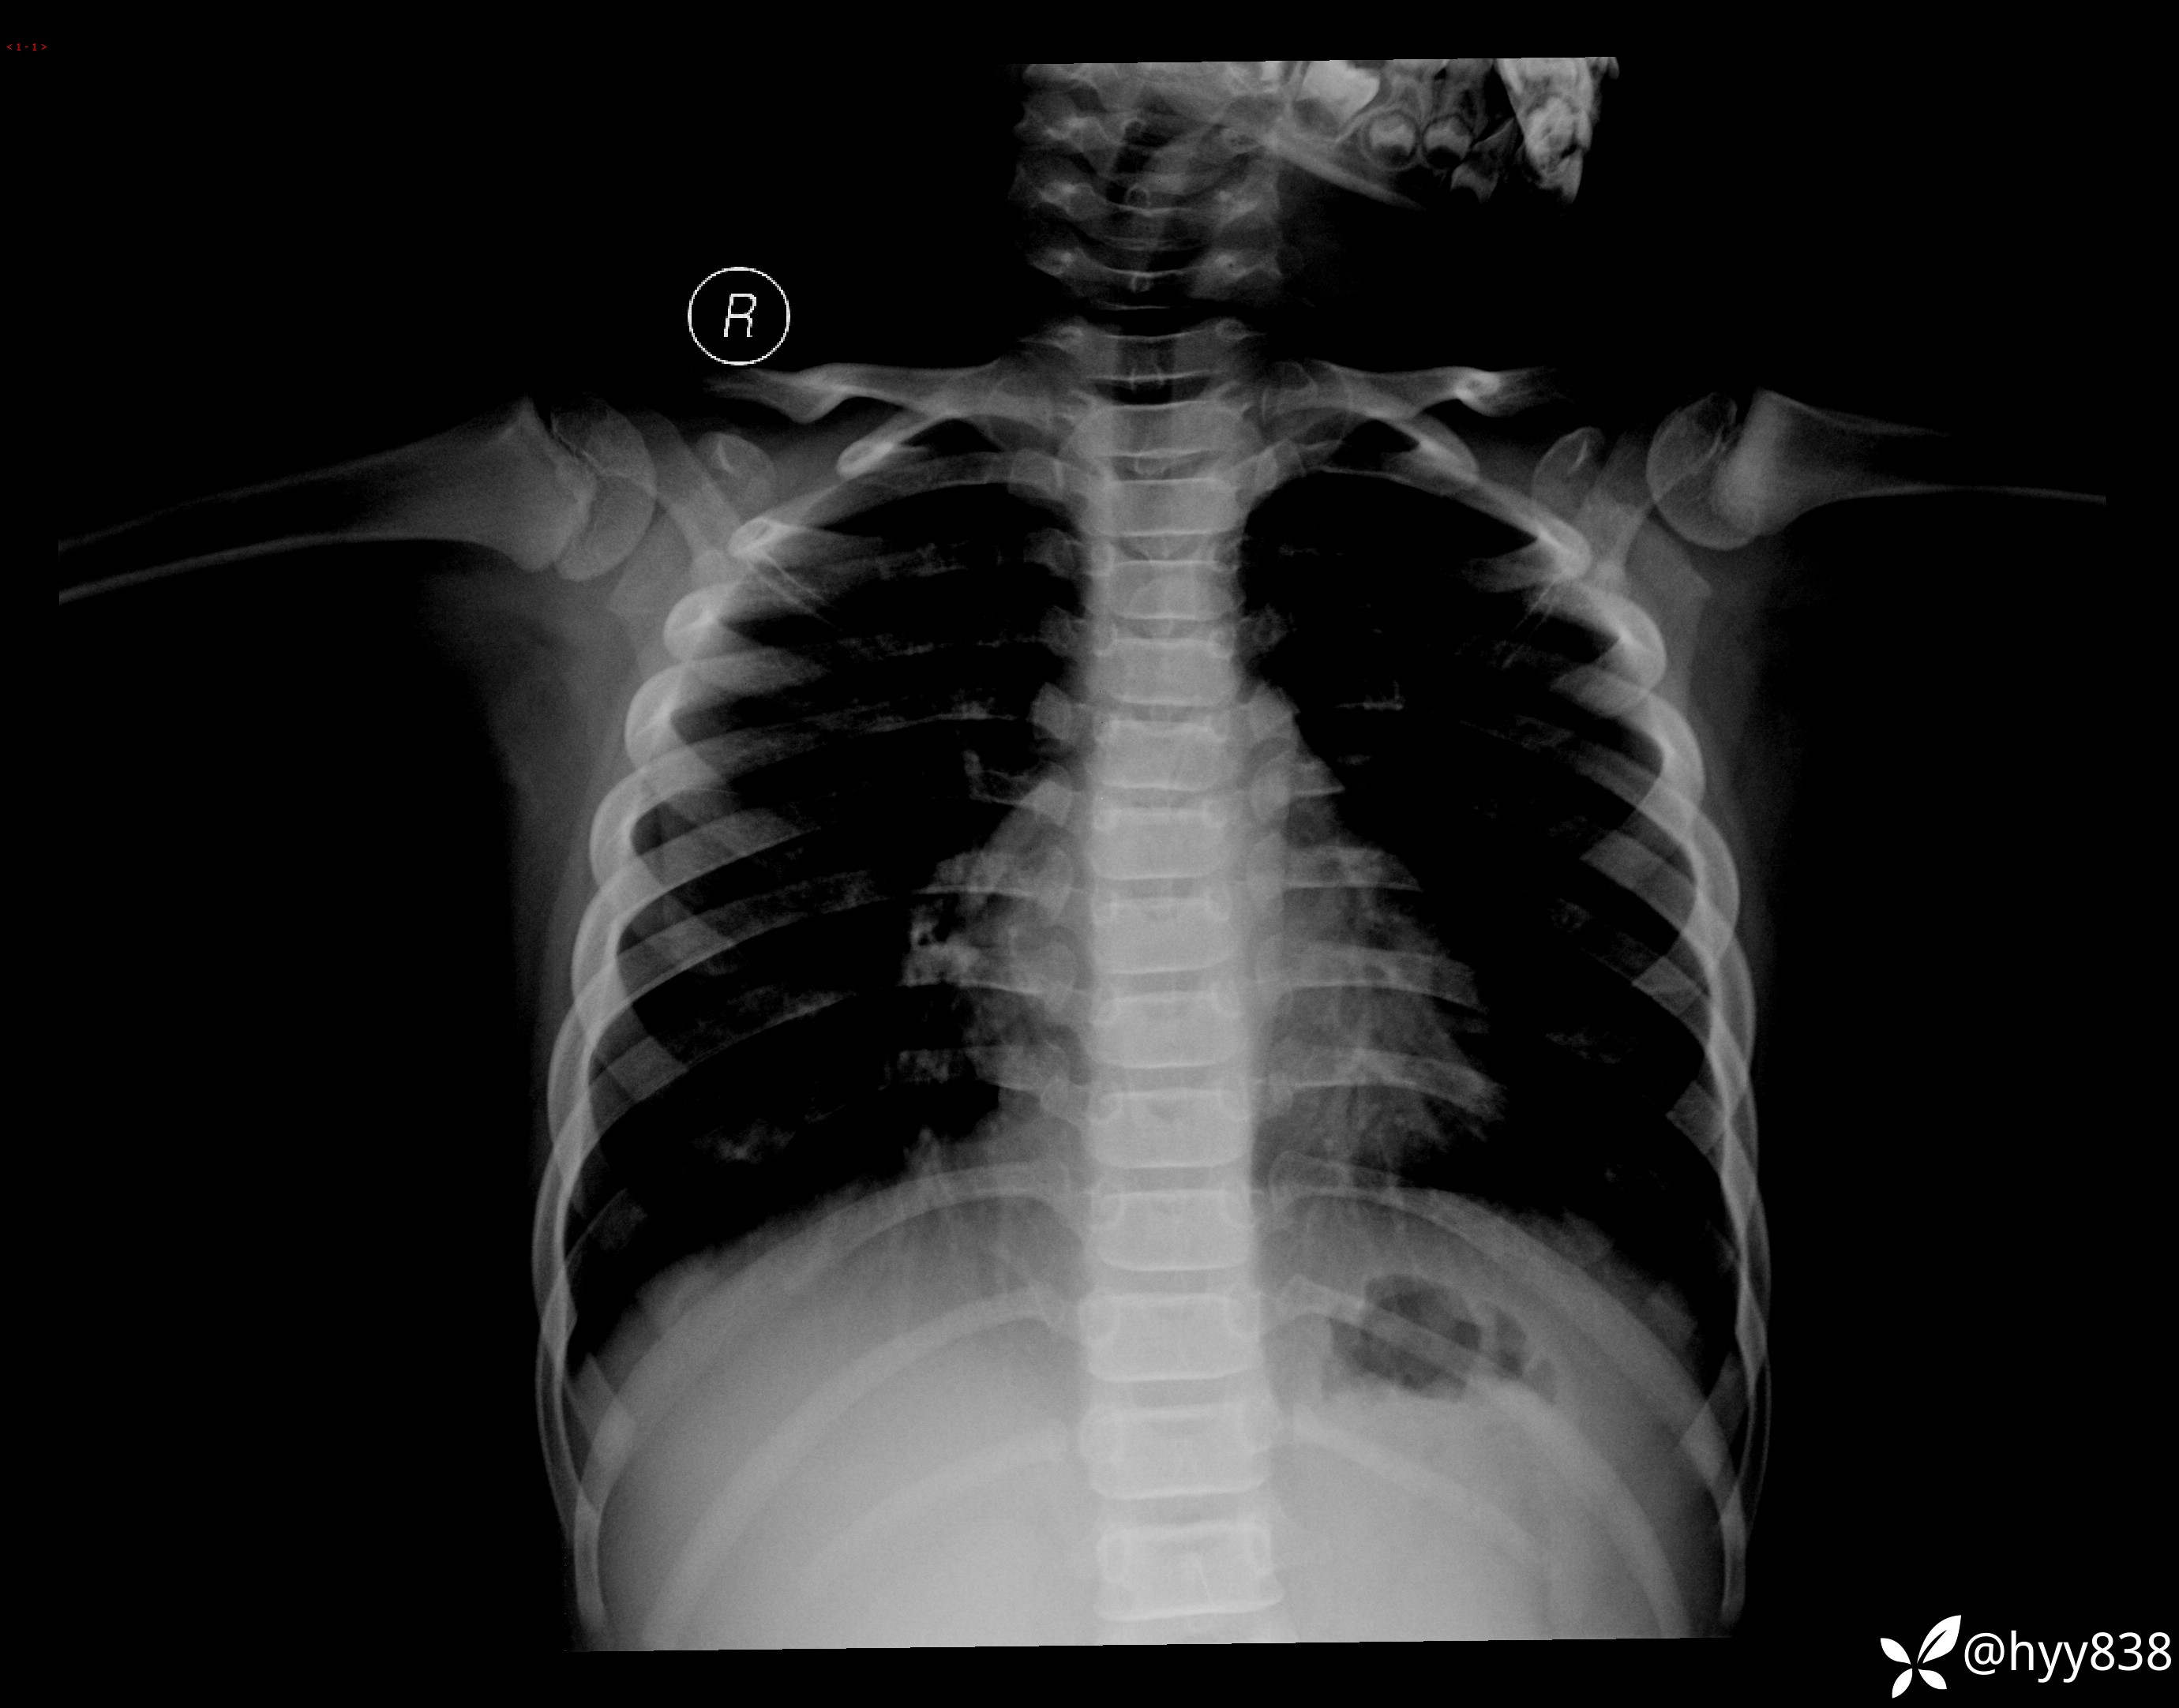

性别:男

年龄:13岁

简要病史:脊柱侧弯复诊

颈椎、胸椎、腰椎正侧位片